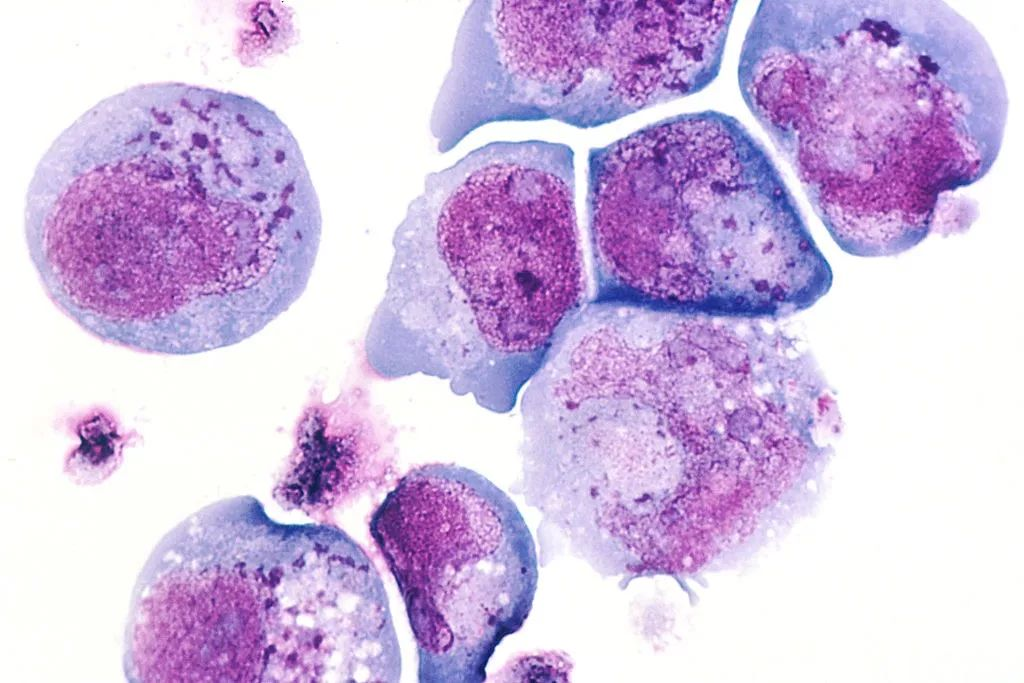

3D版的水痘-带状疱疹病毒

人类疱疹病毒

人类疱疹病毒的组织学切片显示受感染的细胞,包括细胞核和细胞质中的包涵体

EBV病毒